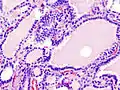

Hyperthyroidism is one of the most common endocrine conditions affecting older domesticated housecats. In the United States, up to 10% of cats over ten years old have hyperthyroidism.[61] The disease has become significantly more common since the first reports of feline hyperthyroidism in the 1970s. The most common cause of hyperthyroidism in cats is the presence of benign tumors called adenomas. 98% of cases are caused by the presence of an adenoma,[62] but the reason these cats develop such tumors continues to be studied.

The most common presenting symptoms are: rapid weight loss, tachycardia (rapid heart rate), vomiting, diarrhea, increased consumption of fluids (polydipsia), increased appetite (polyphagia), and increased urine production (polyuria). Other symptoms include hyperactivity, possible aggression, an unkempt appearance, and large, thick claws. Heart murmurs and a gallop rhythm can develop due to secondary hypertrophic cardiomyopathy. About 70% of affected cats also have enlarged thyroid glands (goiter). 10% of cats exhibit "apathetic hyperthyroidism", which is characterized by anorexia and lethargy.[63]